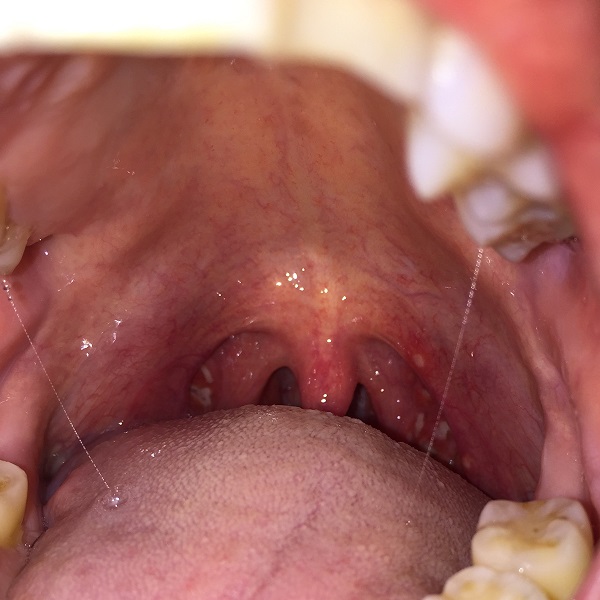

Last week I came down with acute tonsillitis, and every word I said, every bite I took, and every sip I took, I paid with excruciating pain. Thankfully I am over it now.

acute tonsillitis

急性扁桃腺炎 = acute tonsillitis